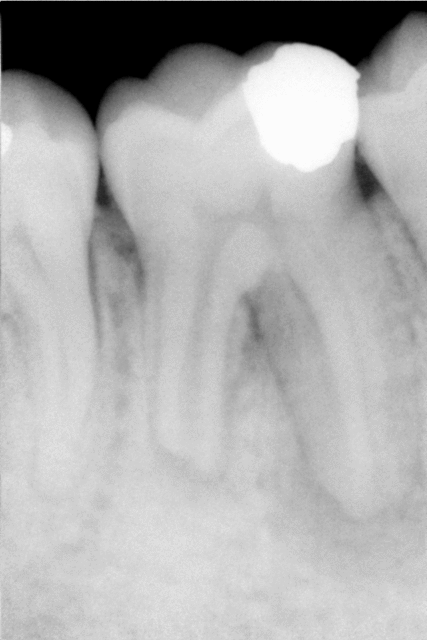

Je reprends de retour de vacances, BONNE ANNEE !!Donc lo17 pour le distal, qui saignait (je tiens a jour mes dossiers), a peine je passe une lime de 08 a 17 plus 0.01 que le saignement repart, je suis en forme je décide de fermer cet apex au MTA a n’en pas douter il est complètement explosé ! Manque de réflexion, non juste pas de radio cone en place ! Sic …

Je place mon produit sous micro, sans problème, mon cerveau génialissime a trouvé la solution à ce problème. HEHEHE. Radio...sic.

A ce stade je n’ai pas eu besoin de trop réfléchir, le patient a repris place sur le fauteuil, et j’ai vérifié la lo a la radio…lo 19mmm !!?? Je sort le bout de gutta il ne tient pas et il n’est pas souillé a l’apex ? Donc re preparation, re irrigation, et miracle, plus de saignement, je termine de façon plus conventionnelle et radio.

Bon pour l’abcès il semble que j’ai la réponse, mais quid du saignement a lo-2mm ? Réponse si le conne flottait il semble que le problème n’était pas apical. Vraiment ce saignement m’intrigue.

oui, et tu l'aurais pas obturé nickel cette fois..il me semble voir une fusée de pate canalaire à ce niveau sur ta dernière radio?

Alors je ne parlerais pas au conditionnel, pour moi cela me semblait clair et repondre à la premiere question: abces paro ou endo? reponse: abces endo due au canal lateral on est bien d'accord.

Non mon probleme c'est pouquoi ca saigne abondement meme à la deuxieme sceance apres l'hydroxyde de calcium, dans le canal à LO-2mmm? J'ai du mal à crore que c'est ce petit canal lateral qui saigne comme si "l'apex etait explosé"!

Je travaille sous microscope et le canal palatin (et voilà je ne me relis pas et ca recommence...distal bien sur distal ;), une erreur et tout de suite des reponses :)) avait une forme de 8, sans separation, avec ce cone de gutta de 35 invisible avant de passer au delà de 17mm, zonne dans laquelle je n'osais pas rentrer avant. Apres preparation jusqu'à la LO 19, l'apex etait bien visible le canal lateral non, et cela ne saignait plus. La zone d'ou provennait l'hemoragie contenait bien un cone de gutta!

L'apex de la racine distale n'est pas grande forme , en plus de cette probable rhizalyse , tu en as peu être une autre au milieu de la racine (en extérieur) mais au niveau de la furcation qui communique avec le canal , d'où le saignement abondant .( Je me demande si je suis clair ?!?!?).

L'apex il ne me semblait pas si mal vue au micro mais au milieu non il n'y avait rien, la pression lors de l'obturation l'aurait peut etres mise en evidence, vu que le lateral pas si gros c'est rempli.?